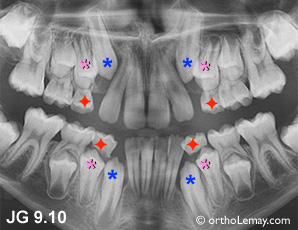

JG 9.10

palais femme de 68 ans

Canine incluse (*bleu) logée dans le palais derrière l’incisive centrale (*mauve) et latérale (*orange) d’une femme de 68 ans.